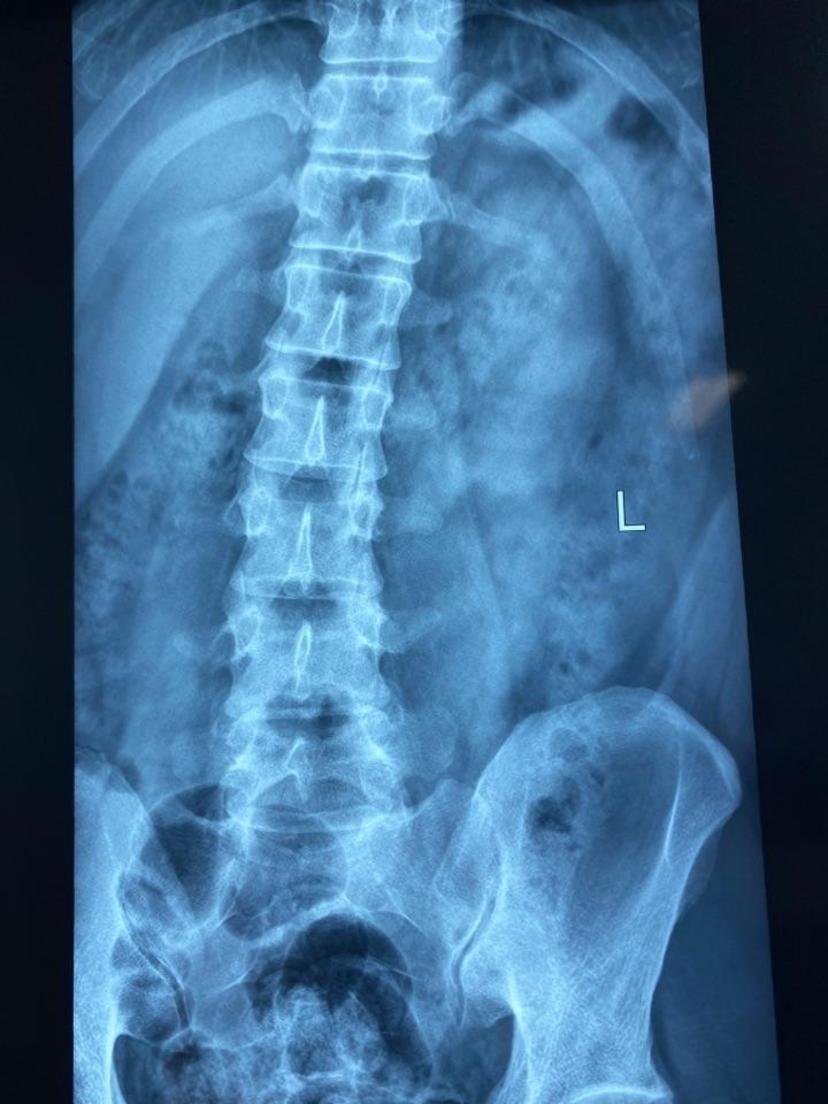

患者近4个月,腰痛及左下肢胀痛麻木,不能正常走路、不能平躺,术程半小时,局部麻醉下取出巨大髓核,切口0.5cm,即刻不适症状完全消失,术后次日正常走路,开心康复出院!由于长期疼痛,出现脊柱继发性侧弯